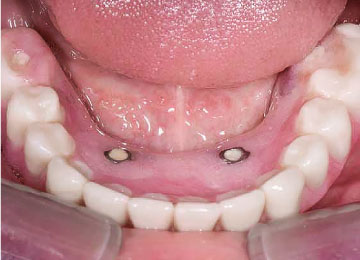

Имплантация зубов: фото "До" и "После"

Фото ДО

Фото ПОСЛЕ

Наведите для просмотра

All-on-4